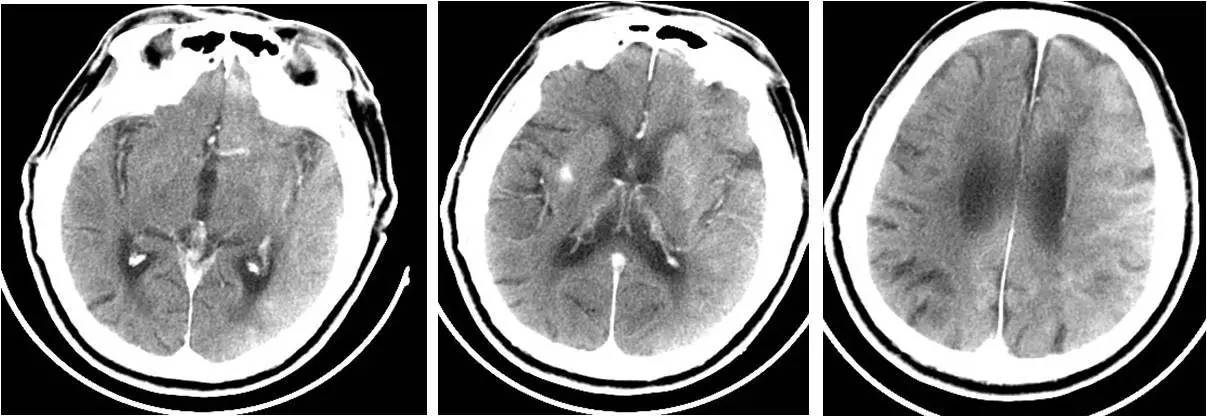

不同时间CT表现